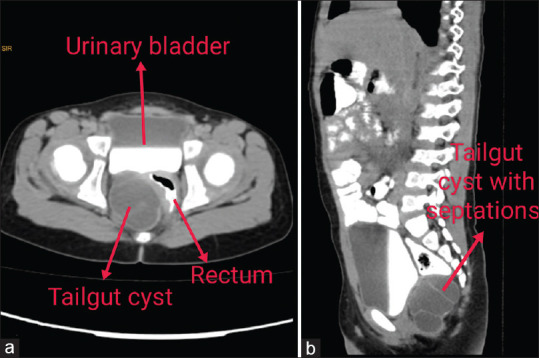

Abstract: Tailgut cysts are rare congenital abnormalities that develop due to failure of embryologic tailgut to involute. This generally manifests as a presacral, retrorectal and multicystic mass. It has a high propensity in female patients including paediatric age group. The clinical presentation varies depending on the age of patient, location and size of the cyst. The symptoms are mostly due to mass effects and rarely complications such as malignancy. Being a rare entity, it is generally misdiagnosed. Differential diagnosis mostly includes rectal duplication cyst, sacrococcygeal teratoma and anterior meningocele. Radiological imaging such as computed tomography scan and magnetic resonance imaging is useful in the diagnosis. The treatment of choice is complete excision to prevent recurrence, infection and malignant degeneration. We have reviewed previous literature and given our valuable information regarding the same.